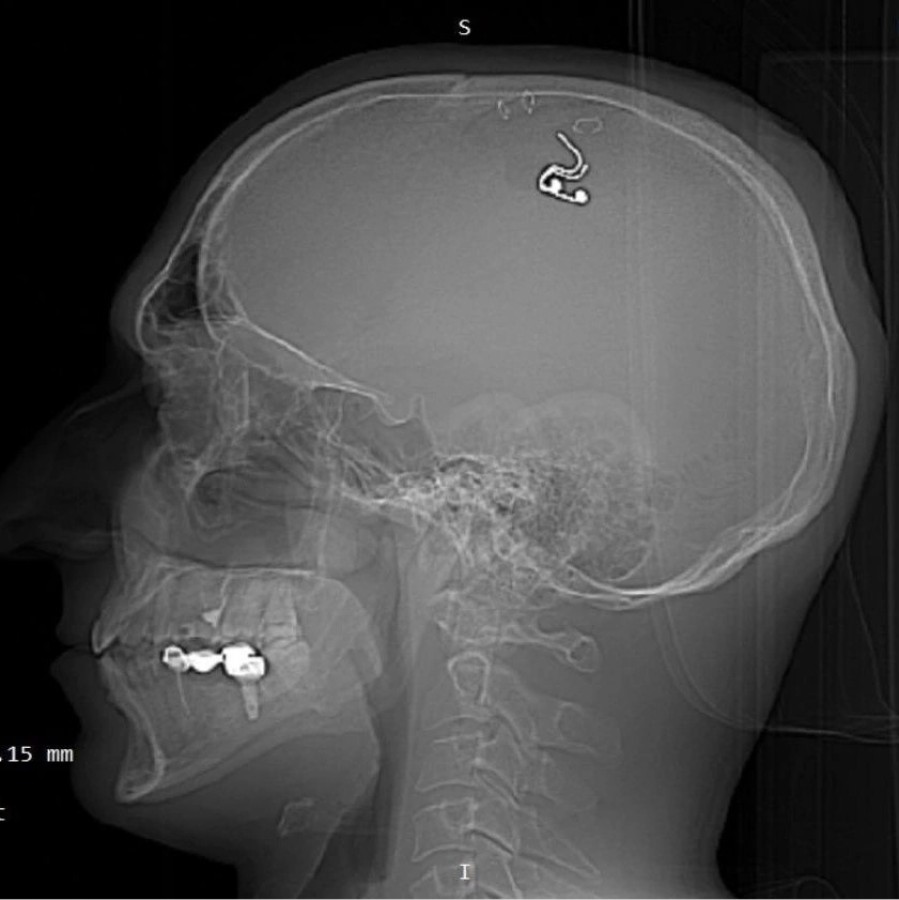

Bir süre sonra çipi kafasına yerleştirmeye karar veren Raduga, matkapla kafatasını deldi. Kan kaybetmeye başladığını fark eden Raduga, en yakın hastaneye başvurdu. Ameliyata alınan Mikhail Raduga'nın kafatasına yerleştirdiği çip çıkarılırken, hayati tehlikeyi atlattığı açıklandı.